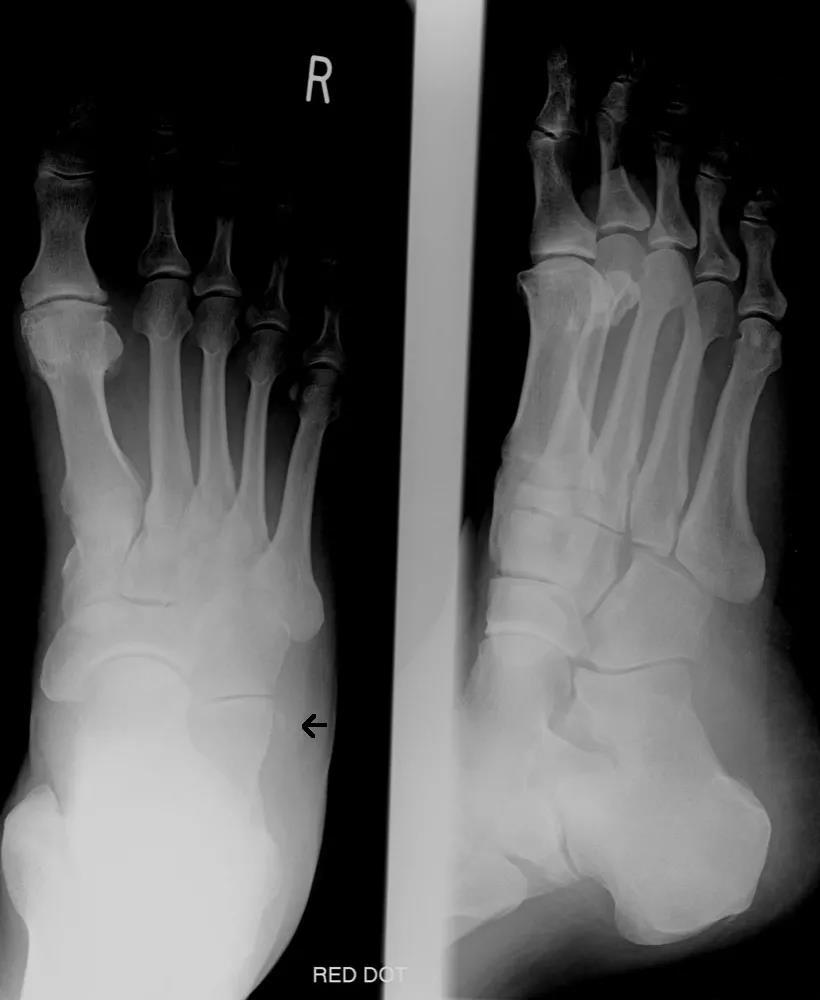

足部肿胀压痛诊断详述

长和水平长):跟骨骨折后缩短 2,宽度:增加 3,高度:降低 4,bohlers角

跟骨两个角度:bohler′s角(以跟骨后关节面后上缘为顶点,分别连接骰骨

跟骨结节关节角,即bohler角,是跟骨结节上缘(跟骨结节与跟骨后关节突

解剖 bohlers角:缩小,消失或反角 反映后关节面的塌陷 gissans

跟骨结节关节角(bohler角)即跟骨结节上缘(跟骨结节与跟骨后关节突的